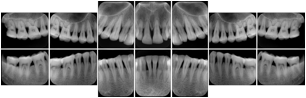

Intra-oral radiography typically involves acquisition of multiple images of various parts of the dentition. Many digital radiographic systems offer customized templates that are used for displaying the images in a study on the screen. These templates may also be referred to as mounts or view sets. The Structured Display Object represents a standard method of encoding and exchanging the layout and intended display of Structured Displays. A structured display object created in this manner could be stored with a study and exchanged with images to allow for complete reproduction of the original exam.

In most standard cases, images are oriented in structured layouts. These structured displays are useful to be shared between providers for reference purposes.

Table OO.1.1-1 shows structured display standard templates, where Viewset ID is based on the Japanese Society for Oral and Maxillofacial Radiology (JSOMR) classification provided by JIRA (Japan Medical Imaging and Radiological Systems Industries Association, www.jira-net.or.jp). Expected or typical teeth to be imaged location, region and designation codes are based on ISO 3950-2010, Dentistry - Designation system for teeth and areas of the oral cavity. For all the hanging protocols listed in OO.1.1-1, the value to use for Hanging Protocol Creator (0072,0008) is "JSOMR" and the value to use for Hanging Protocol Name (0072,0002) does not include "JSOMR" (e.g., "DL-S001A", not "JSOMR DL-S001A").